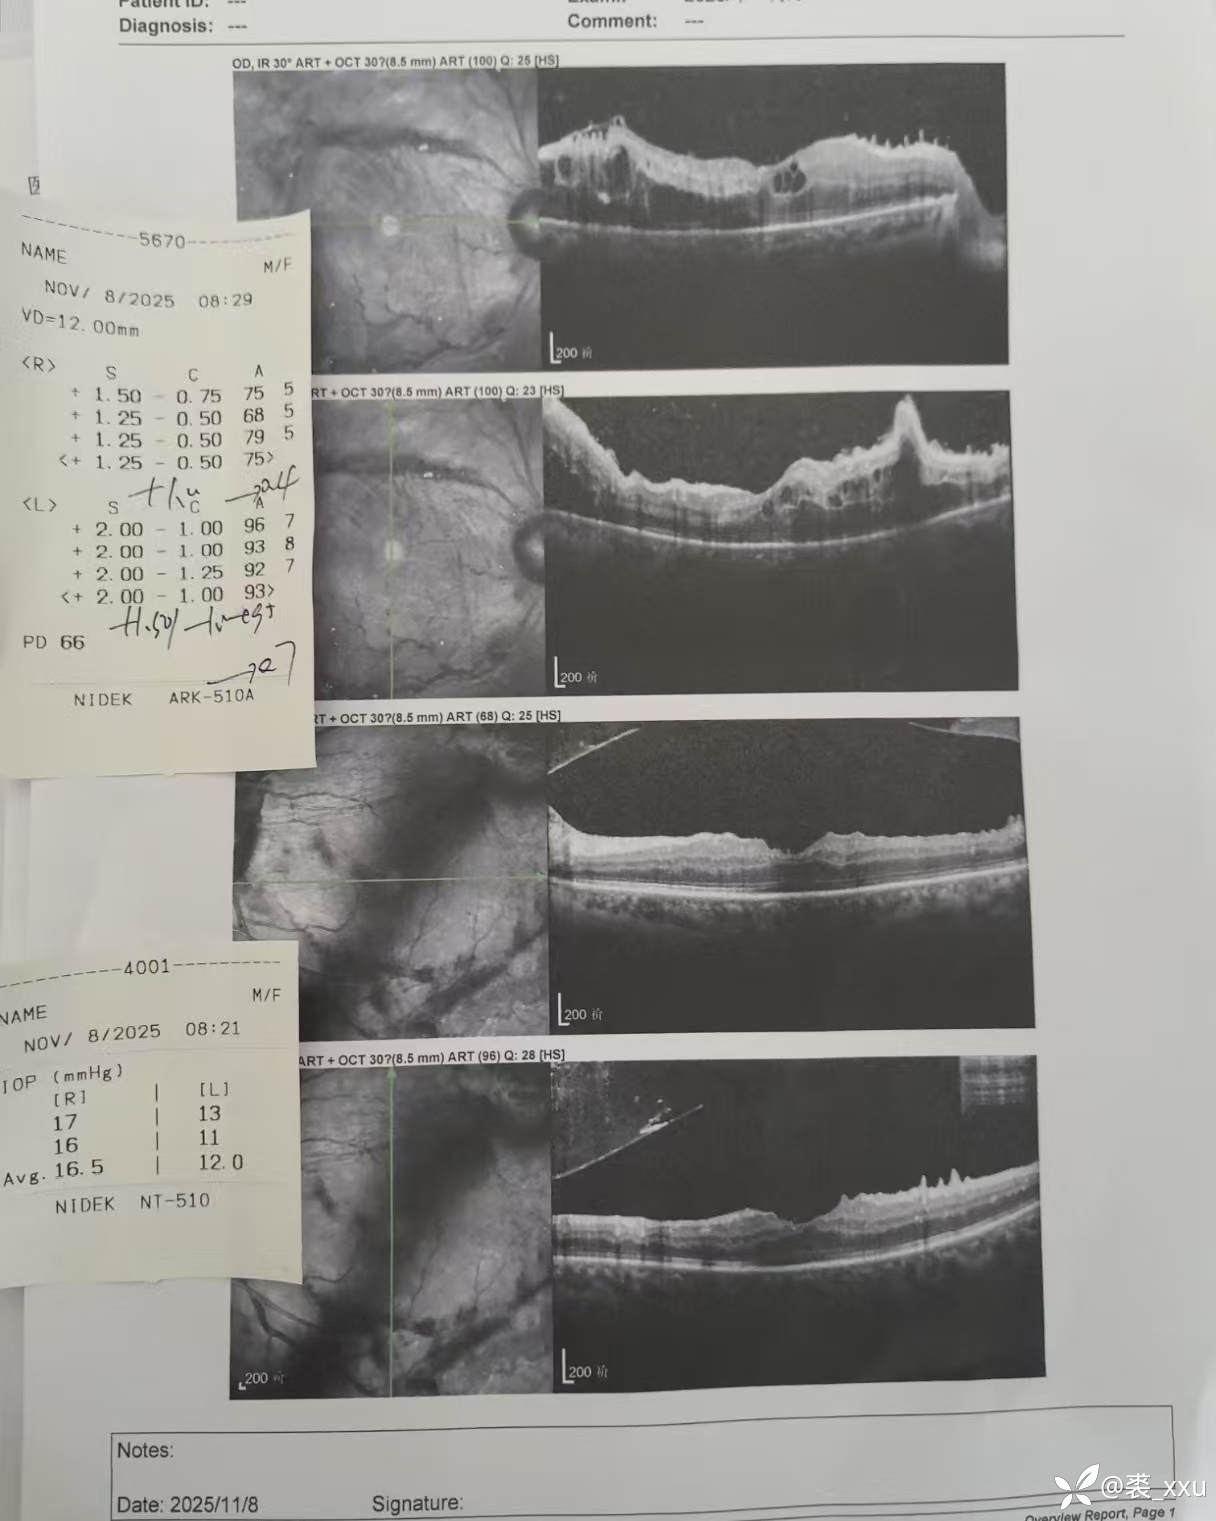

糖网6期,已出现牵拉裂孔,糖网牵拉裂孔一般不会和常规网脱一样视网膜容易飘动,切膜困难,因为其下为粘稠的网膜下液,但如出现医源性裂孔进入灌注液切膜剥膜将会很困难。所以该病例做的比较保守,切膜不彻底,部分残留。

这些残留的增殖膜会不会导致后续的问题,有没有必要即使可能出现医源性裂孔术中也要彻底清除干净?

这种牵拉裂孔脱离的患者不打气打油安全吗?